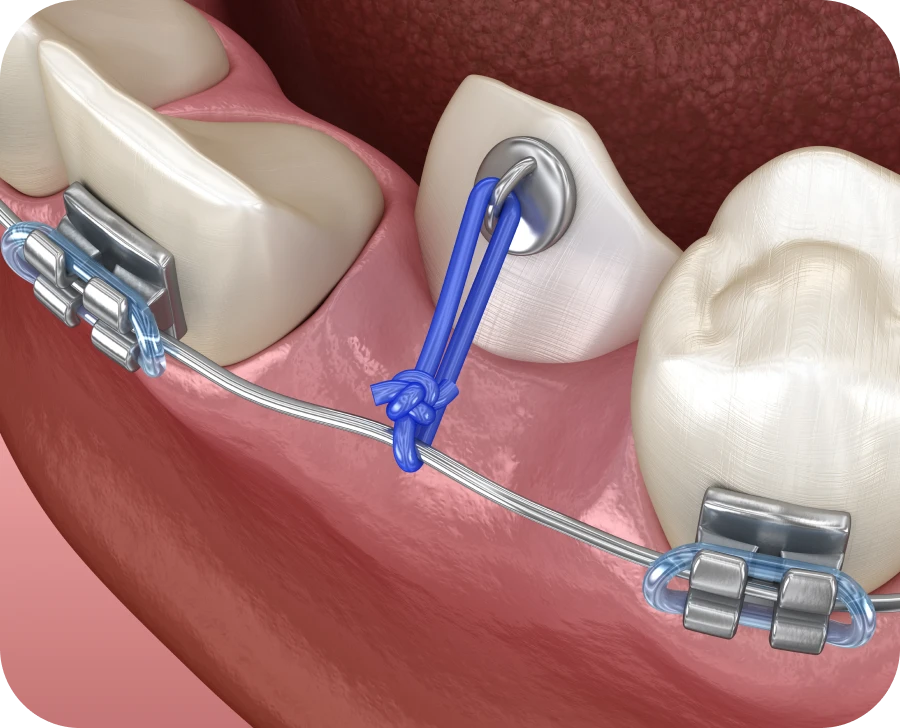

Par la suite, une traction orthodontique est souvent mise en place. Une attache est alors fixée sur la dent, qui est doucement guidée à l’aide d’un fil. Il convient d’ajuster progressivement la force de traction afin de ne pas fragiliser la racine. Des rendez-vous réguliers permettent de suivre l’évolution et de réajuster le traitement si besoin.

Certaines dents sont plus souvent concernées par une inclusion. C’est notamment le cas des canines maxillaires. Leur éruption doit être surveillée dès l’âge de 9 ans. Lorsqu’elles sont orientées vers le palais, une désinclusion chirurgicale est souvent nécessaire. Un traitement interceptif permet alors de dégager leur chemin d’éruption. Une fois la dent exposée, une attache collée permet de guider sa progression vers la bonne position.